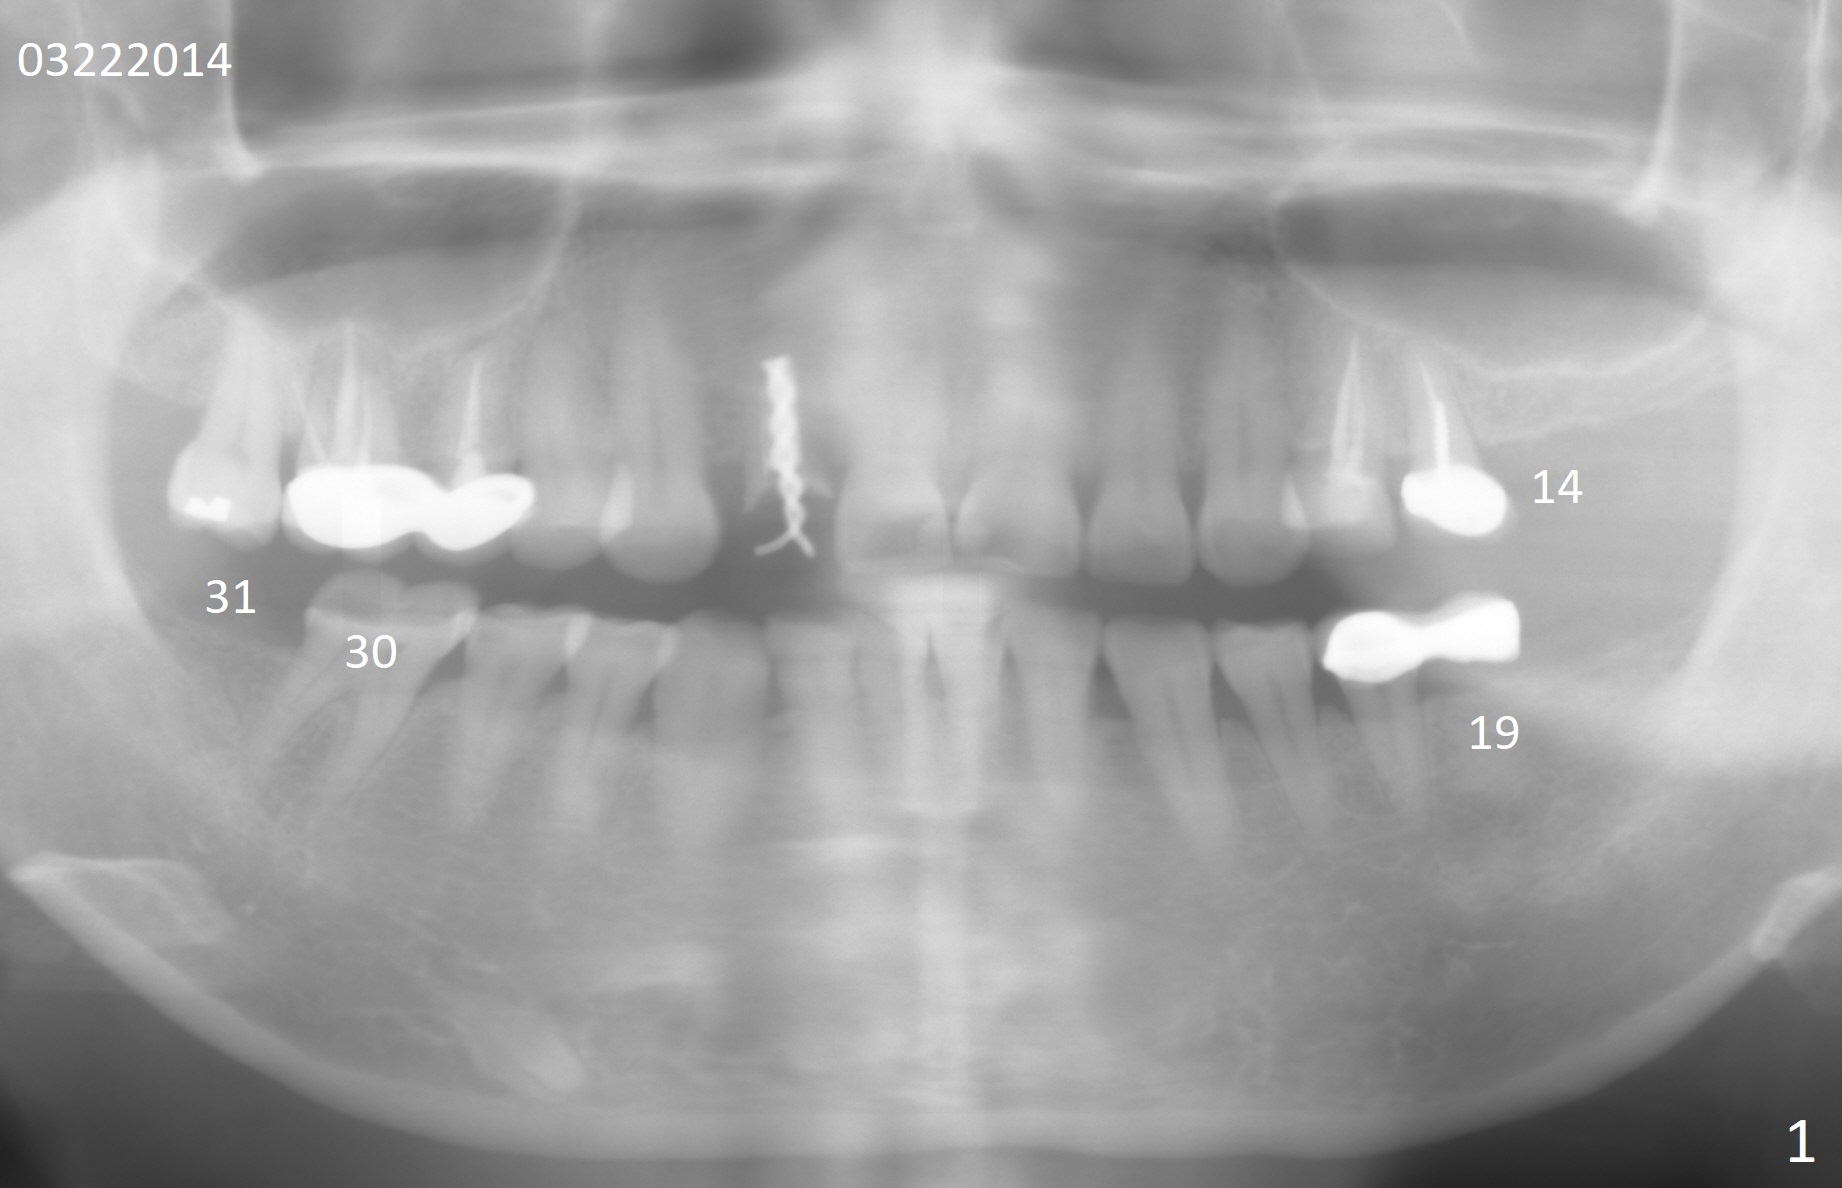

A 50-year-old healthy woman is determined to have implant placement at #14, 19 and 31 because of severe wear at #30. Crown will be fabricated at #30 first. The lower left cantilever bridge will be sectioned prior to CT and impression for scanning. Which implant should be placed first?